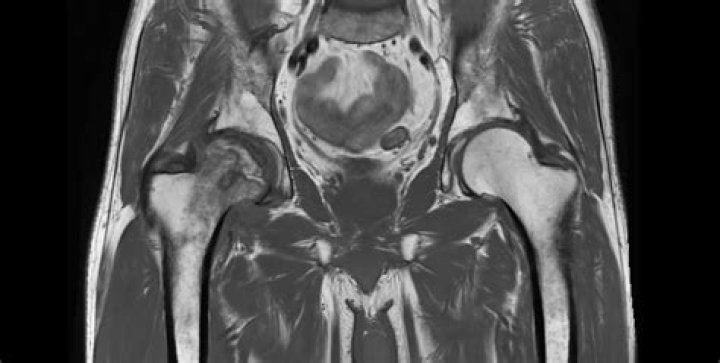

MRI findings of AVN include decreased signal intensity in the subchondral region on both T1- and T2-weighted images, suggesting edema (water signal) in ea...